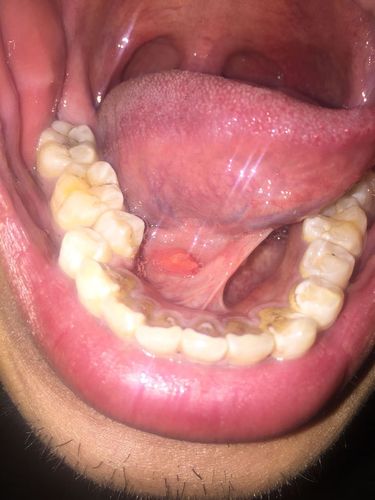

口腔里,舌头下面,但不是舌头上长了个肉芽.

会不是会是艾滋病?

舌头根部长了一个肉芽一样的东西,白色的,突出来的.有